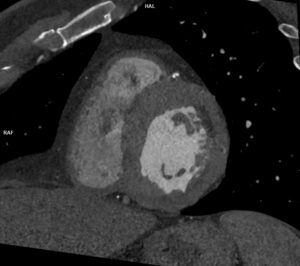

Discuţie caz nr 96: Boală Barlow este un sindrom clinic datorat prolapsului de valvă mitrală; se evidențiază deplasarea în sistolă a cuspelor mitrale spre atriul stâng ce asociază disjuncţie de inel mitral și fenomen de curbare posterioară. Această forțare a miocardului ventricular stâng din segmentele laterale poate duce la apariția de arii de fibroză că substrat aritmogen – materializate sub formă de priză de contrast (nu e cazul la acest pacient).